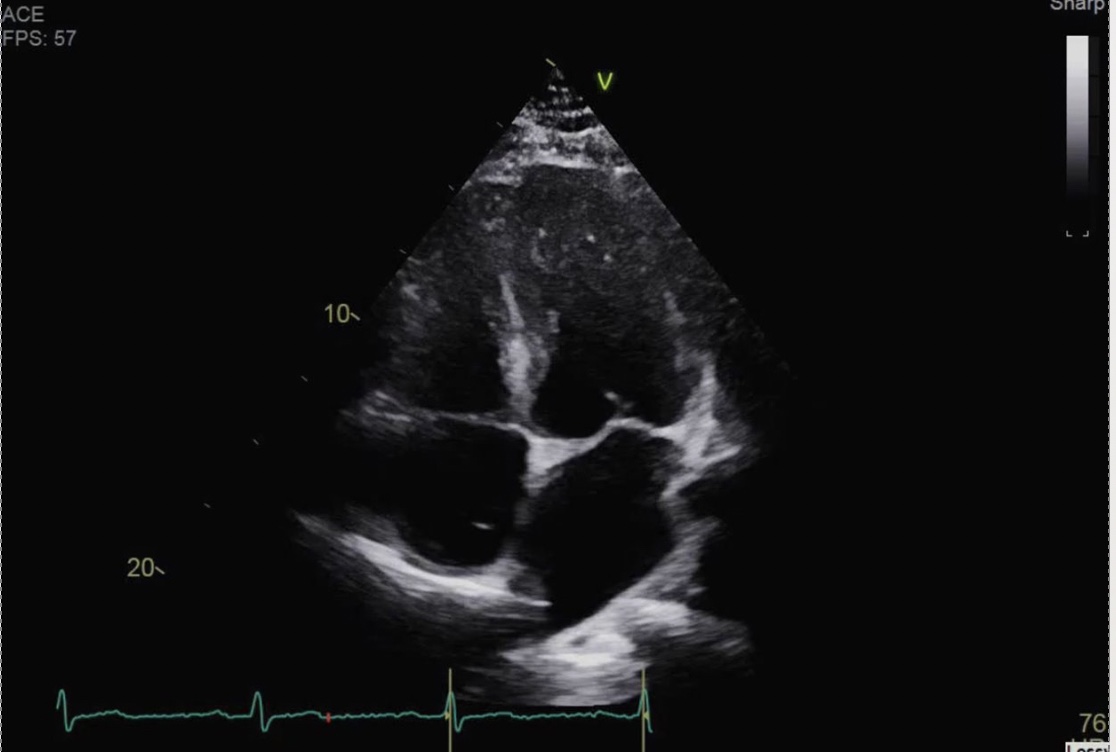

Identify the view and structures

Apical 4 chamber